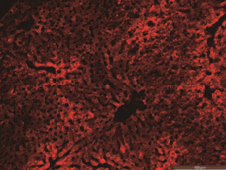

肝脏